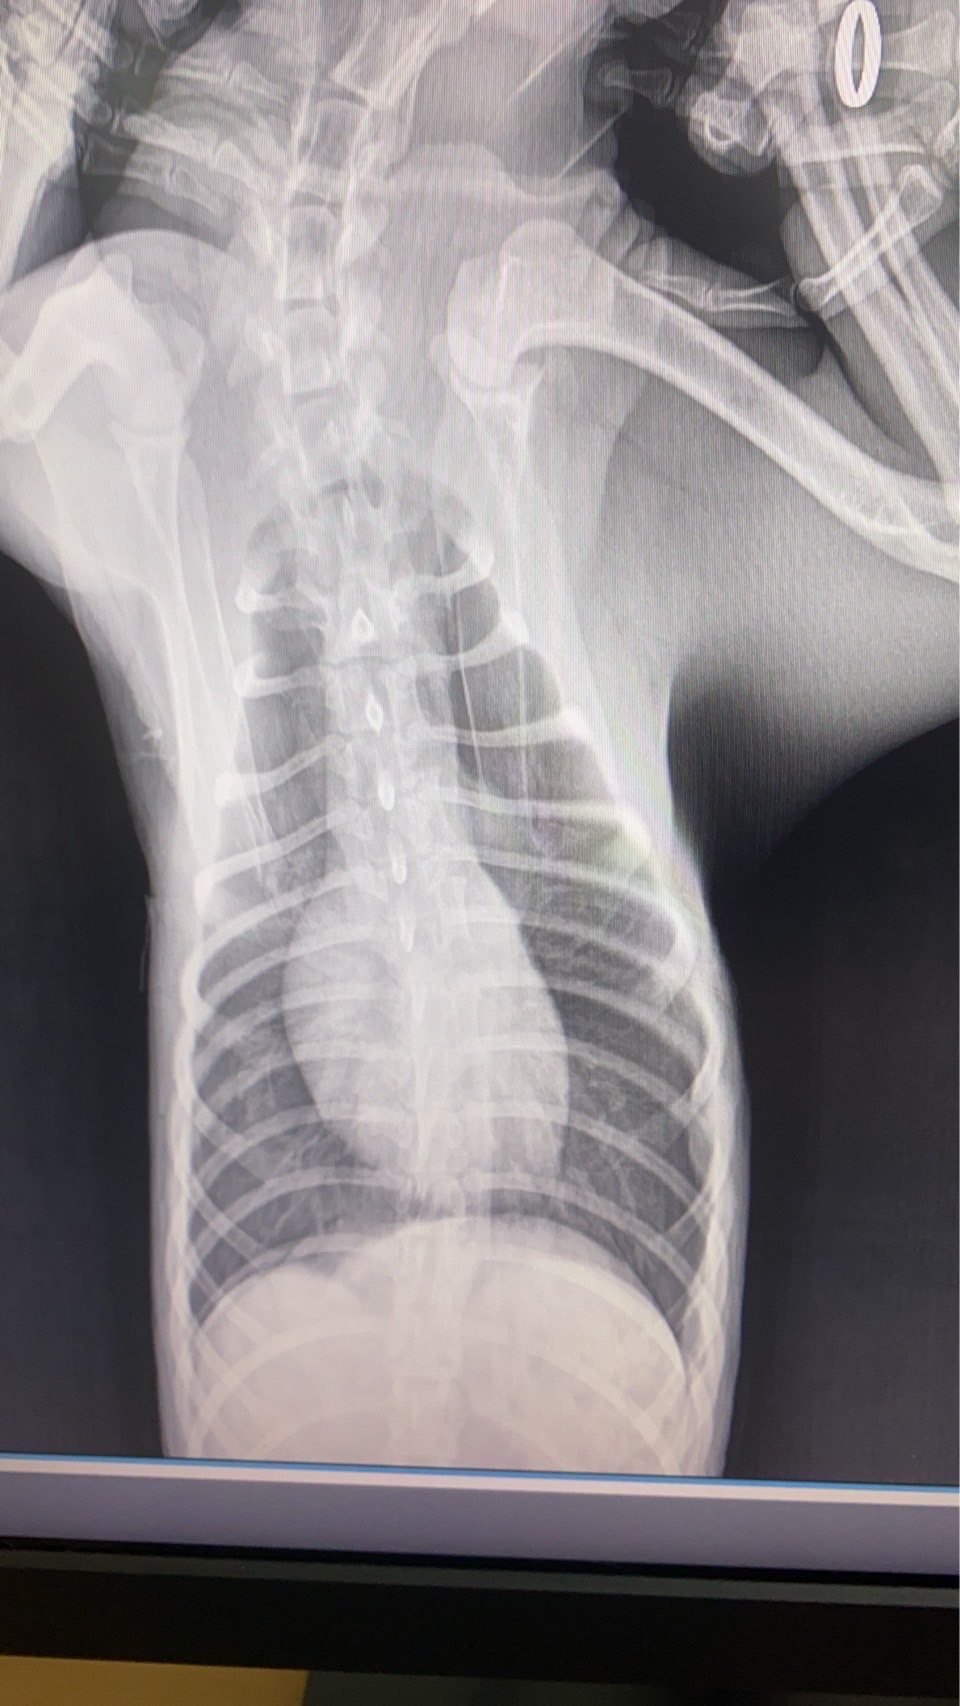

ทีมสัตวแพทย์ของเราได้รับเคสฉุกเฉินจากอุบัติเหตุที่ทำให้สัตว์เลี้ยงตัวหนึ่งได้รับบาดเจ็บรุนแรง กะบังลมฉีกขาดส่งผลให้อวัยวะในช่องท้องเคลื่อนเข้าไปในช่องอก ทำให้เกิดภาวะหายใจลำบาก หลังจากตรวจวินิจฉัยด้วยภาพรังสี ทีมสัตวแพทย์ได้ตัดสินใจเข้าผ่าตัดแก้ไขโดยการเย็บกะบังลม และจัดอวัยวะกลับสู่ตำแหน่งปกติ ผลลัพธ์เป็นที่น่าพอใจ น้องสามารถหายใจได้ตามปกติและกลับมาใช้ชีวิตได้อย่างมีความสุข โรงพยาบาลสัตว์ของเราพร้อมดูแลสัตว์เลี้ยงทุกตัวด้วยทีมแพทย์ผู้เชี่ยวชาญ หากพบอุบัติเหตุหรือภาวะฉุกเฉิน